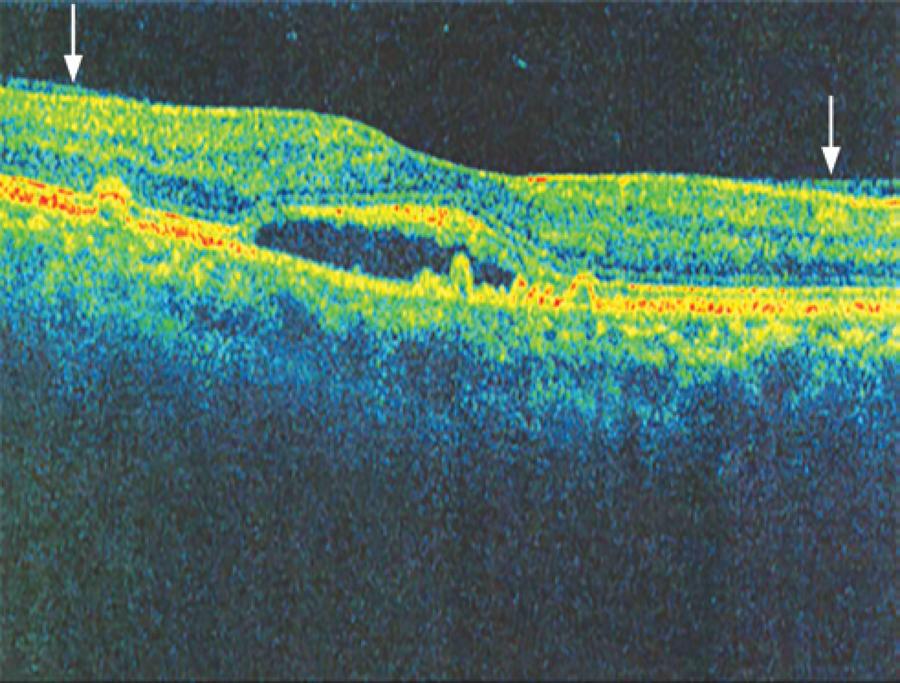

In six patients with AMD, SD-OCT revealed vitreoretinal adhesion (Figure 1), whereas USG detected two cases of partial posterior vitreous detachment (PVD), with both being adherent to the macula, as shown in figure 2 (in four cases, there was no PVD). In the 25 cases of AMD in which the hyaloid was not visible by SD-OCT (Figure 3), USG detected total PVD in five eyes, mobile vitreous membranes in six eyes, and partial PVD in 14 eyes (adherent to the optic nerve). In one of the two cases in which SD-OCT revealed total detachment of the hyaloid in the macular area, while USG revealed no detachment.

Figure 1 Image obtained with spectral domain optical coherence tomography (Cirrus HD-OCT), showing the hyaloid adhering to the macular area (arrows).